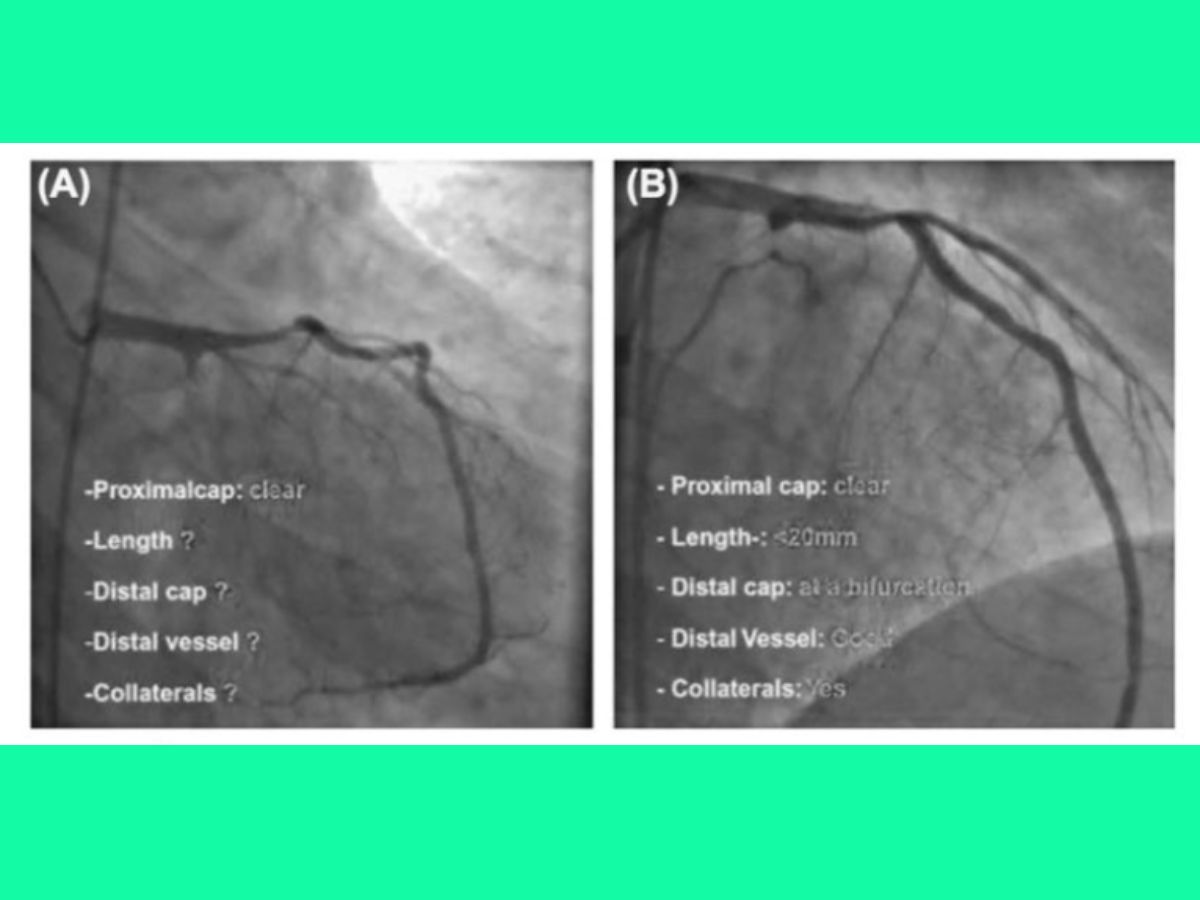

Đường tiếp cận

Tiếp cận bằng 2 đường và bơm cản quang kép (dual injection – chụp đồng thời mạch vành trái và phải) là kỹ thuật đơn giản và hiệu quả nhất để tăng khả năng thành công và giảm biến chứng khi can thiệp CTO, nên được thực hiện trên tất cả CTO có tuần hoàn bàng hệ đối bên, ngay cả khi chỉ can thiệp xuôi dòng.

Vai trò của bơm cản quang kép giúp đánh giá chính xác hơn của độ dài và đặc điểm của tổn thương CTO, thấy được vị trí đầu dây dẫn can thiệp khi can thiệp xuôi dòng, giảm tổn thương mạch máu (dưới nội mạc) khi sử dụng kỹ thuật reentry.

(A): Chỉ bơm cản quang vào thân chung; (B): Bơm cản quang kép vào thân chung và động mạch vành phải.